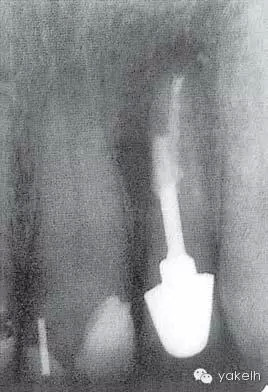

¤¤口外檢查可見(jiàn)顳下頜關(guān)節(jié)處輕微捻發(fā)音,開(kāi)口度、開(kāi)口型正常,無(wú)疼痛,未見(jiàn)其他異常??趦?nèi)檢查可見(jiàn)牙列中有部分良好的修復(fù)體,無(wú)齲壞;局部牙齦炎,探診出血,牙周探診深度不超過(guò)2mm。22唇側(cè)牙槽黏膜可見(jiàn)竇道(圖5.4.1a),輕微叩痛,竇道區(qū)捫痛,根尖X線片顯示牙根中部透射影,疑為樁穿孔(圖5.4.1b)。左上頜中切牙(21)和左上頜尖牙(23)對(duì)EPT和冷測(cè)試反應(yīng)正常。

圖 5.4.1(b)22根尖X線片,顯示樁穿孔側(cè)方的根周透射影。